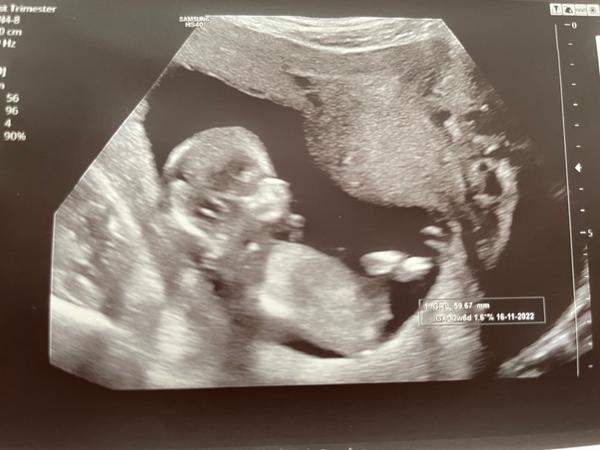

chtěla bych se zeptat, zda lze z této fotky určit pohlaví miminka. Stáří 13+5 tt.